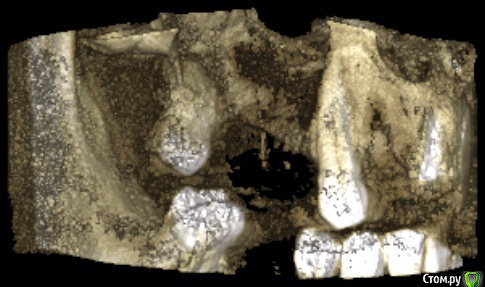

32worldwide Опубликовано 2 июня, 2020 Поделиться Опубликовано 2 июня, 2020 Вот скрины с 3Д. Там видна тень от дренирующей трубки. Вопрос такой же кто как порекомендует вести пациента дальше. И есть отправить на ЧЛХ то что там будут делать(интересно просто)? Ссылка на комментарий

Irouil Опубликовано 5 июня, 2020 Поделиться Опубликовано 5 июня, 2020 Я не уверен, что тут уже что-то вырастет. Вестибулярной стенки нет, протяжённость медио-дистально большая. Если с острой стадией покончили возможно имеет смысл идти на вылущивание и потом планировать реконструкцию Ссылка на комментарий

32worldwide Опубликовано 15 июня, 2020 Поделиться Опубликовано 15 июня, 2020 Спасибо. Вы же зуб удаляли, у Вас больше информации. Если что-то смущает сделайте биопсию). По снимку больше на одонтогенный очаг похоже.Через 3-4 месяца уже будут видны первые изменения.Спасибо.Я не уверен, что тут уже что-то вырастет. Вестибулярной стенки нет, протяжённость медио-дистально большая.Если с острой стадией покончили возможно имеет смысл идти на вылущивание и потом планировать реконструкцию Ссылка на комментарий